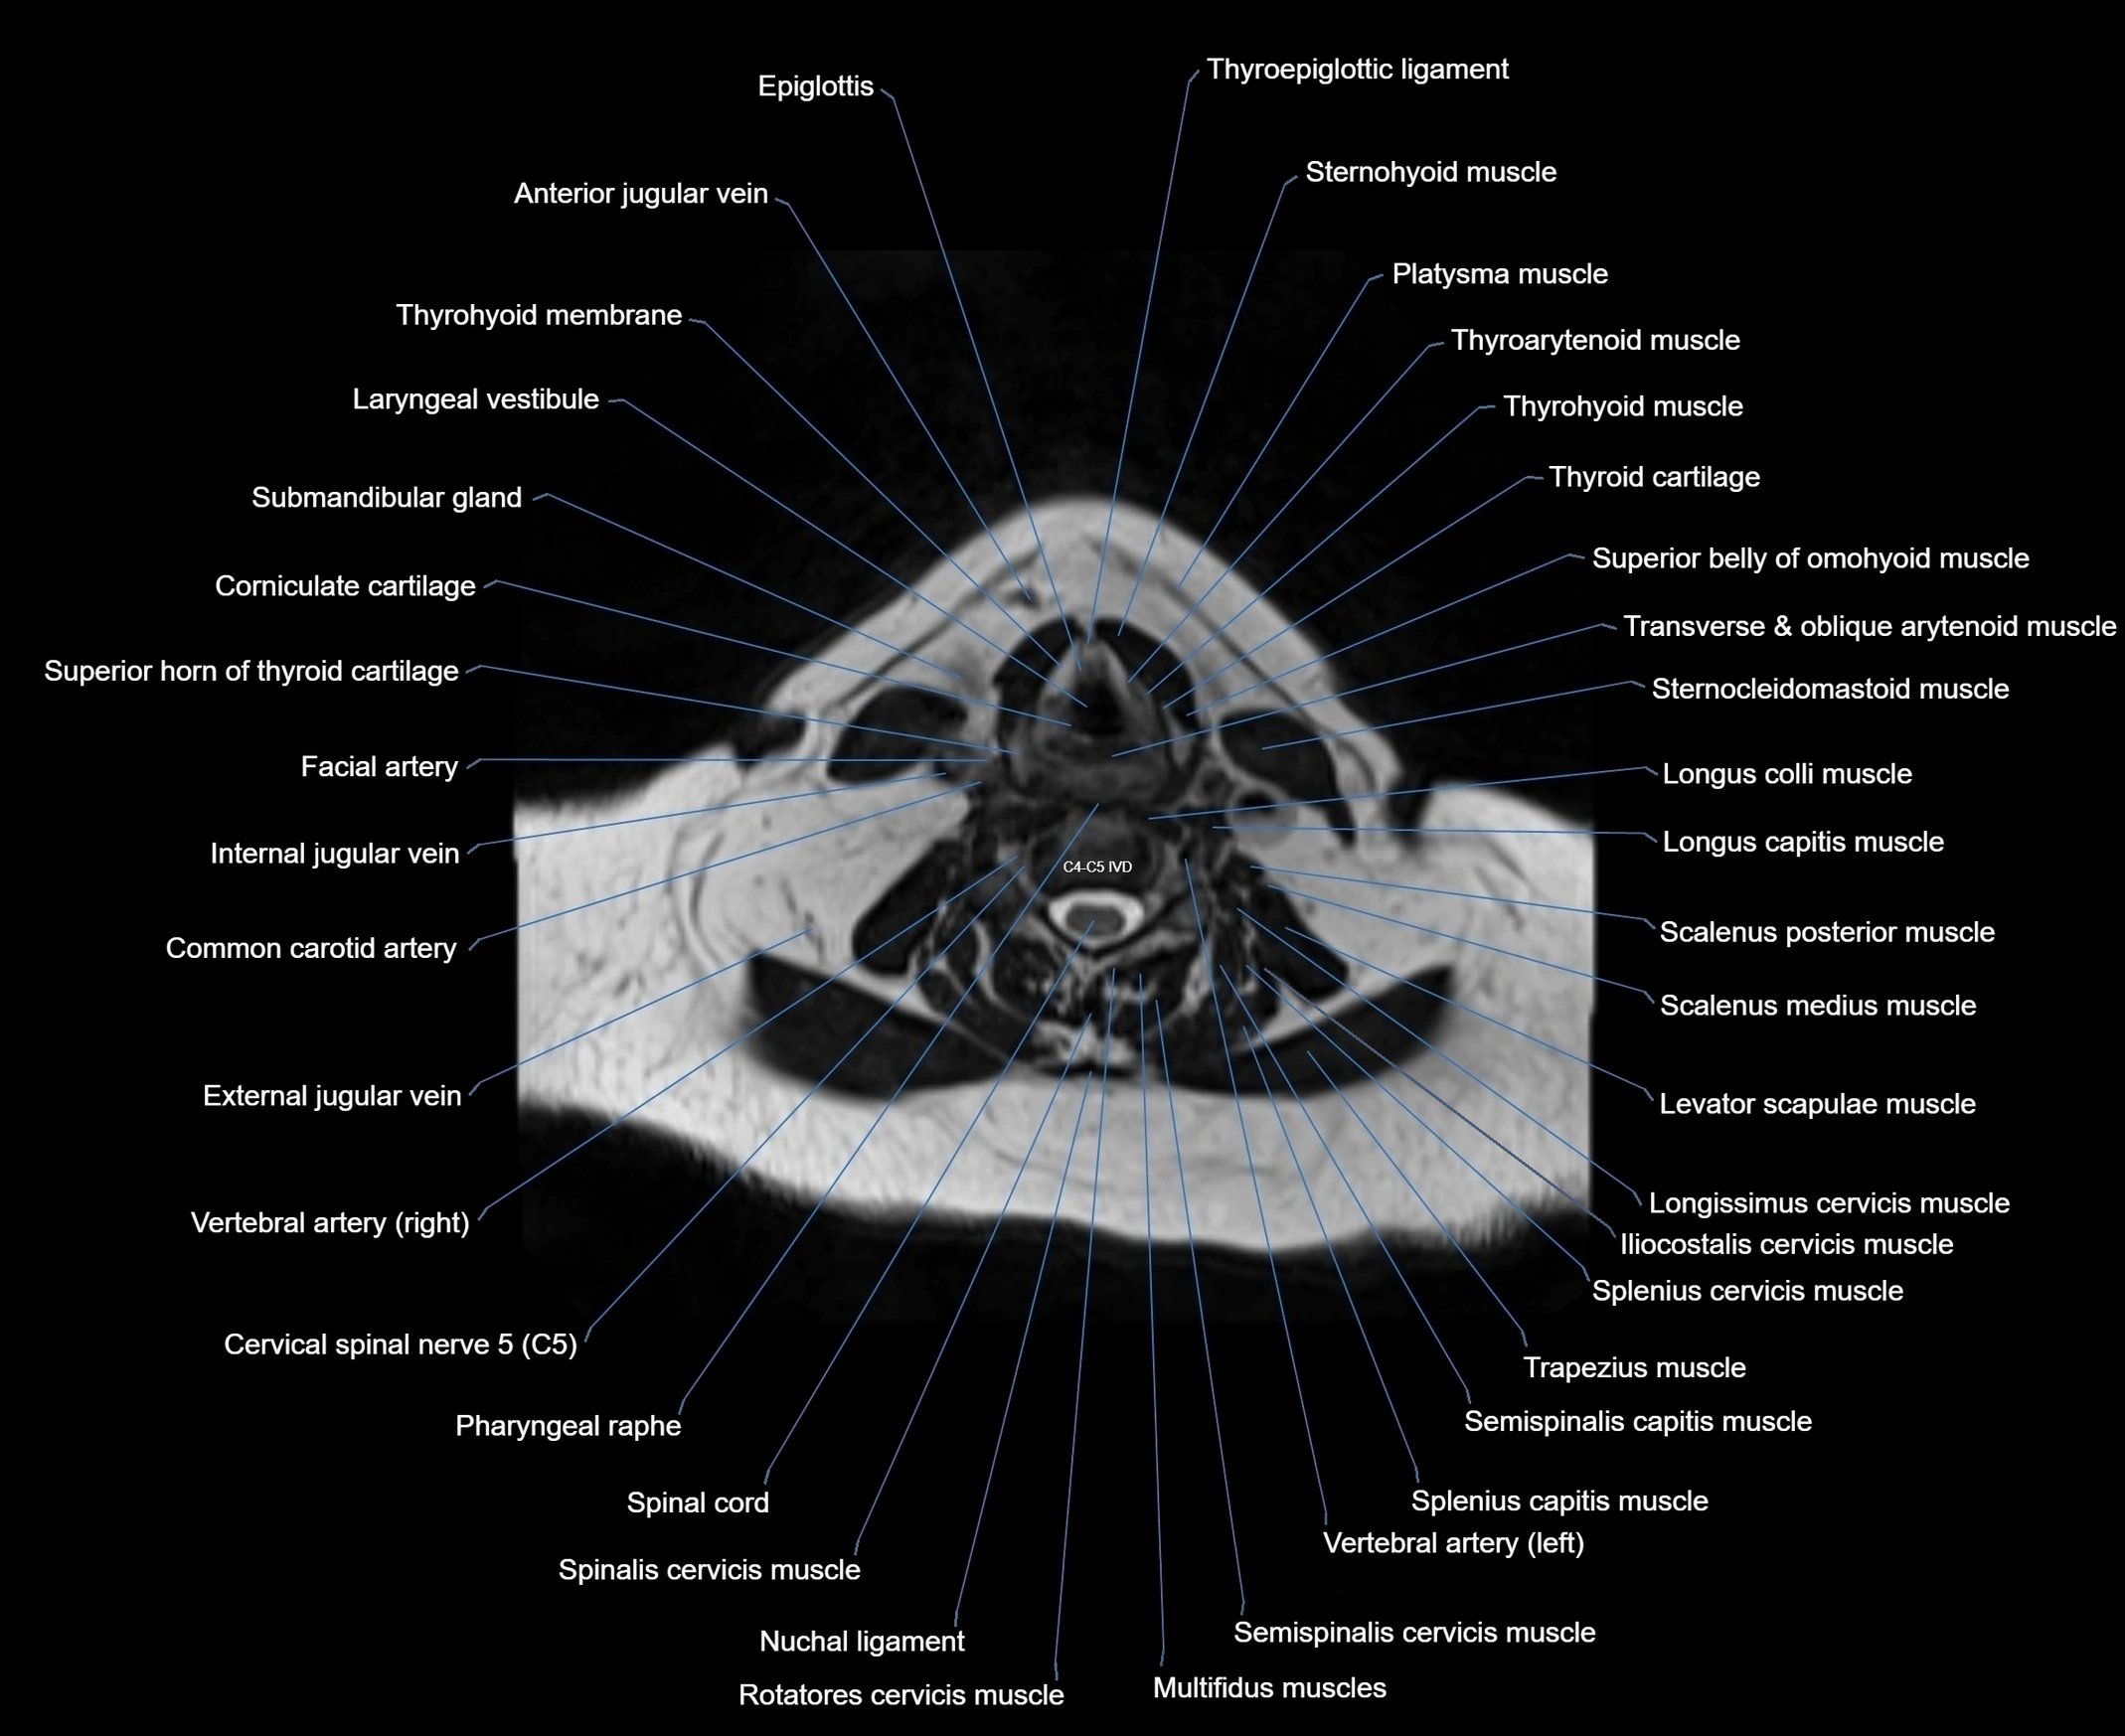

MRI images